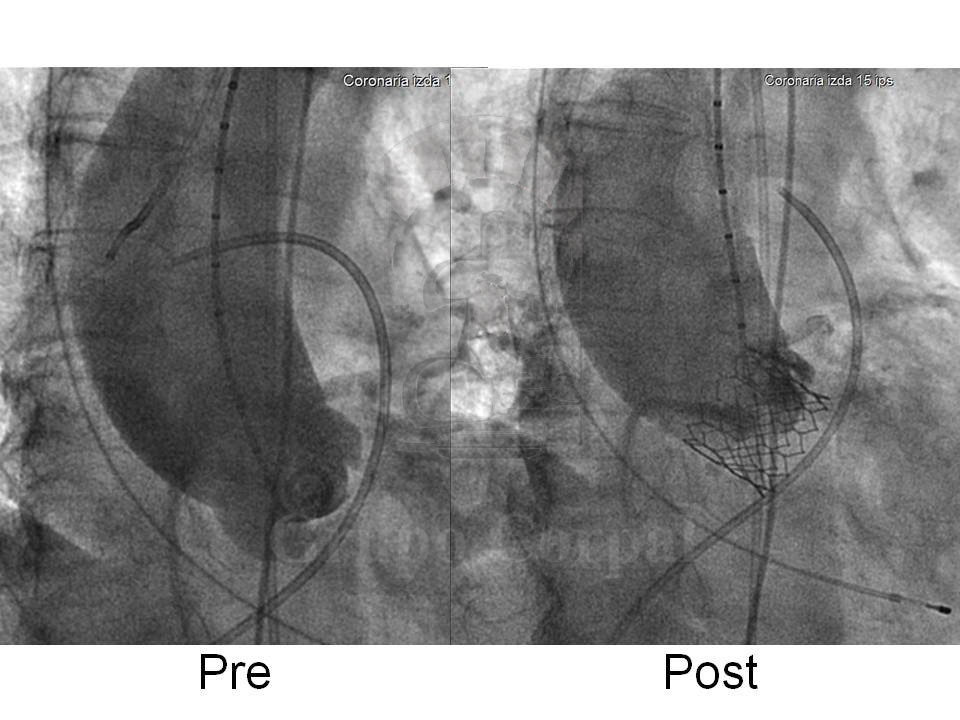

Se presentan las imágenes hemodinámicas y angiográficas antes, durante y después del implante percutáneo de una prótesis valvular aórtica de Edwards de 26 mm en una paciente de 70 años de edad con estenosis aórtica severa y calcificada con válvula bicúspide. El resultado clínico fue excelente y la paciente fue dada de alta a las 72 horas de su ingreso.